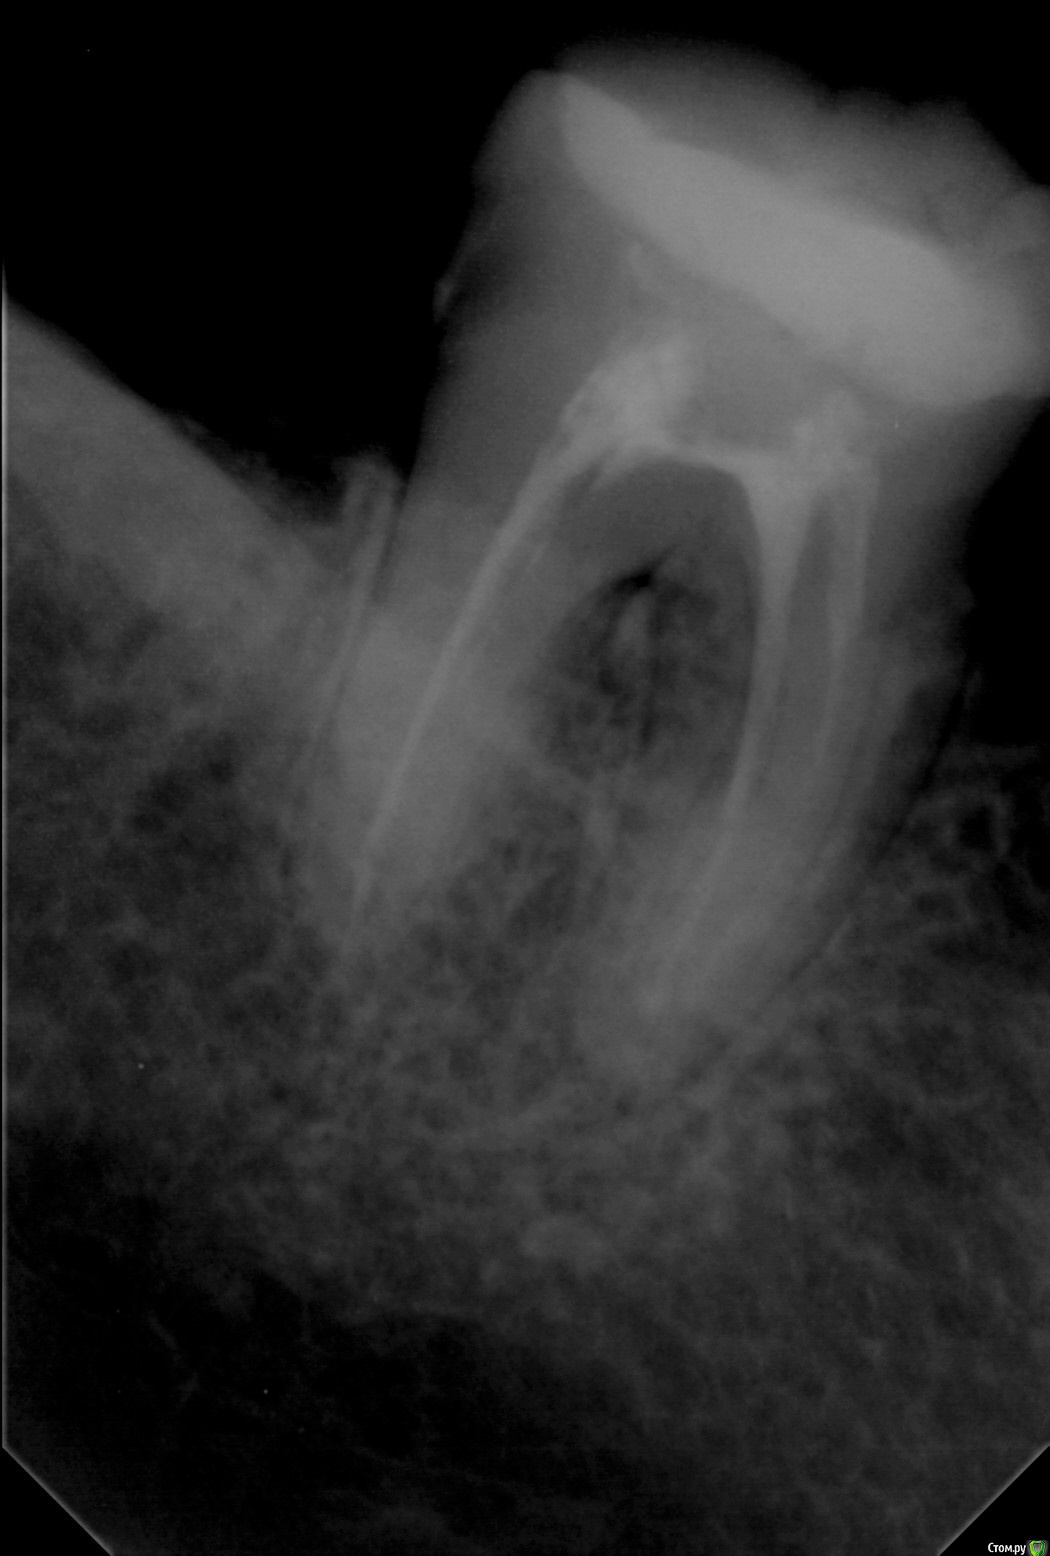

Wedernikoff Опубликовано 1 октября, 2017 Автор Поделиться Опубликовано 1 октября, 2017 А у меня нет другого ;((( как жаль. Мне так нужно решить судьбу 37...мнения разделились. Одни говорят, что он с восполением между корнями, а кто-то, глядя на этот же снимок, говорит, что все нормально, надо снять пломбу, подчистить и восстановить под коронку. Ссылка на комментарий

IvanK Опубликовано 2 октября, 2017 Поделиться Опубликовано 2 октября, 2017 "кисты" не увидел, анатомия у зуба сложная. я бы советовал сделать кт, после - принимать решение 2 Ссылка на комментарий

IvanK Опубликовано 2 октября, 2017 Поделиться Опубликовано 2 октября, 2017 панорамный снимок "мутный"..по прицельному - если судить только глядя на снимок - у меня нет показаний к удалению 1 Ссылка на комментарий

IvanK Опубликовано 2 октября, 2017 Поделиться Опубликовано 2 октября, 2017 Если контролируете свой диабет, то опасаться нечего Без визуального осмотра нельзя говорить на 100%, это будет решать Ваш ортопед,показание к коронке есть. если на кт "киста не выросла", тогда хорошо) Ссылка на комментарий